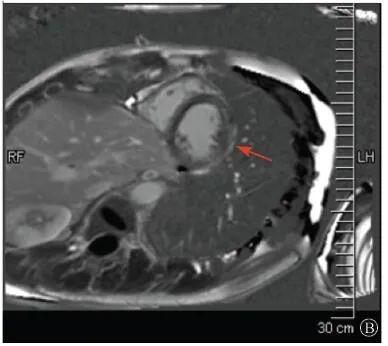

案例介紹:患者男性,20歲,因?yàn)?quot;胸痛4個(gè)月,加重1月余"于2019年7月10日入院?;颊?019年4月無(wú)明顯誘因出現(xiàn)心前區(qū)隱痛,VAS 3分,無(wú)放射,無(wú)胸悶、憋氣、活動(dòng)后氣短,每月發(fā)作1~2次,未在意。同年5月體檢發(fā)現(xiàn),肌酸激酶(CK)2928 U/L、肌酸激酶MB質(zhì)量(CK-MB)46 U/L、心肌肌鈣蛋白I(cTnI)0.055 ng/ml。6月初,患者"感冒"后出現(xiàn)心前區(qū)疼痛加重,為過(guò)電樣疼痛,VAS 5分,無(wú)放射,持續(xù)約30~60 min可好轉(zhuǎn),胸痛每周約發(fā)作2次,否認(rèn)呼吸困難、胸悶、心悸,否認(rèn)活動(dòng)耐量下降。6月8日,患者就診于外院查血生化:CK 1 215→1433 U/L,CK-MB 47 U/L,cTnI 30.17→31.79 ng/L;血脂(-);抗核抗體譜(-);超聲心動(dòng)圖:左室增大,左室舒張末內(nèi)徑57 mm,左室射血分?jǐn)?shù)39%,輕度二尖瓣關(guān)閉不全;磁共振心肌灌注延遲動(dòng)態(tài)成像(圖1):左室稍增大,收縮功能稍減低;基底部至心尖部左室下壁及側(cè)壁、心尖部左室前壁心外膜下心肌纖維化,考慮非缺血性心肌病;肌電圖:肌源性損害(偏慢性)。診斷"多發(fā)性肌炎、心肌損傷",予患者倍他樂(lè)克緩釋片23.75 mg/d、培哚普利0.5 mg/d、螺內(nèi)酯20 mg/d口服,患者未再出現(xiàn)心前區(qū)疼痛,但步行1 km左右會(huì)出現(xiàn)氣短、乏力。為進(jìn)一步明確心力衰竭病因收入我院。患者上高中起出現(xiàn)體育課等劇烈活動(dòng)后雙下肢明顯乏力,不能耐受1 km長(zhǎng)跑類運(yùn)動(dòng),日常體力活動(dòng)不受影響,否認(rèn)肌肉酸痛等不適。此次發(fā)病以來(lái),一般情況尚可,否認(rèn)尿量減少,體重?zé)o明顯變化。既往史:否認(rèn)高血壓、冠心病、糖尿病病史。個(gè)人史:否認(rèn)特殊毒物藥物接觸史,無(wú)煙酒嗜好?;橛?、家族史:未婚未育,否認(rèn)家族類似病史,否認(rèn)遺傳病史。入院查體:脈搏69次/min,血壓112/70 mmHg,指氧(自然狀態(tài))98%,體質(zhì)指數(shù)21.1 kg/m2;無(wú)皮疹;雙肺呼吸音清;心律齊,未聞及雜音;肝脾不大;雙側(cè)腓腸肌肥大,肌肉無(wú)壓痛;四肢肌力Ⅴ級(jí)、肌張力正常。雙下肢不腫。輔助檢查:入室床旁超聲心動(dòng)圖提示左室壁運(yùn)動(dòng)普遍減低,心尖部、左室下后壁為著,肌小梁增多。

左室壁較廣泛心外膜下延遲強(qiáng)化,可見(jiàn)左室下后壁肌小梁增多(箭頭所示)

圖1 患者外院磁共振心肌灌注延遲動(dòng)態(tài)成像